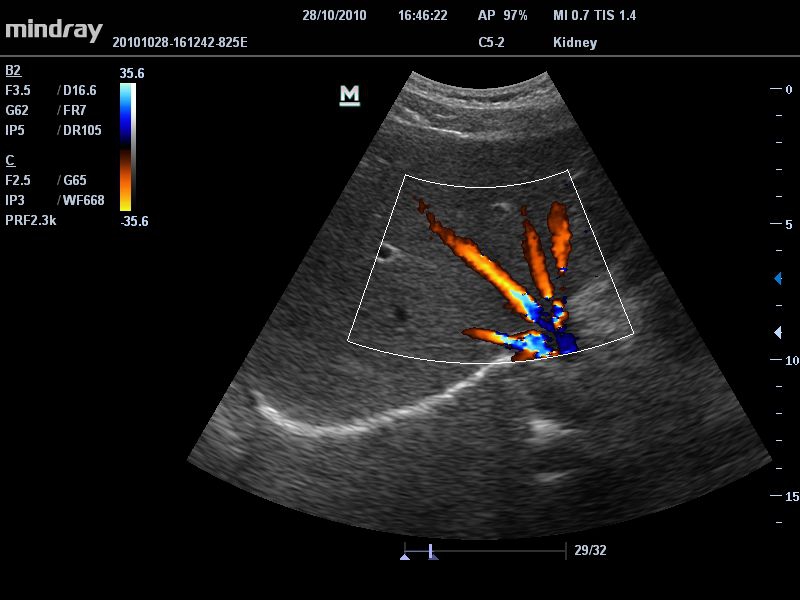

Ультразвуковая система Mindray DC-T6 – это инновационный аппарат для проведения высокого уровня диагностики с качественной визуализацией и широким спектром применения. Платформа рекомендована для использования в коммерчески многопрофильных медицинских учреждениях и государственных лечебных клиниках.

Да

• Режимы сканирования: B/M/CFM/PDI/Направленный PDI/PW, HPRF, Тканевая гармоника, М- и цветной М-режим.